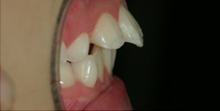

反対咬合(はんたいこうごう)、受け口

下あごが前に出てしまった状態。

顔つきだけでなく、前歯への負担が大きく将来的に歯を失う原因になります。

永久歯列で治療を行う場合、外科手術を伴う事もあります。 -